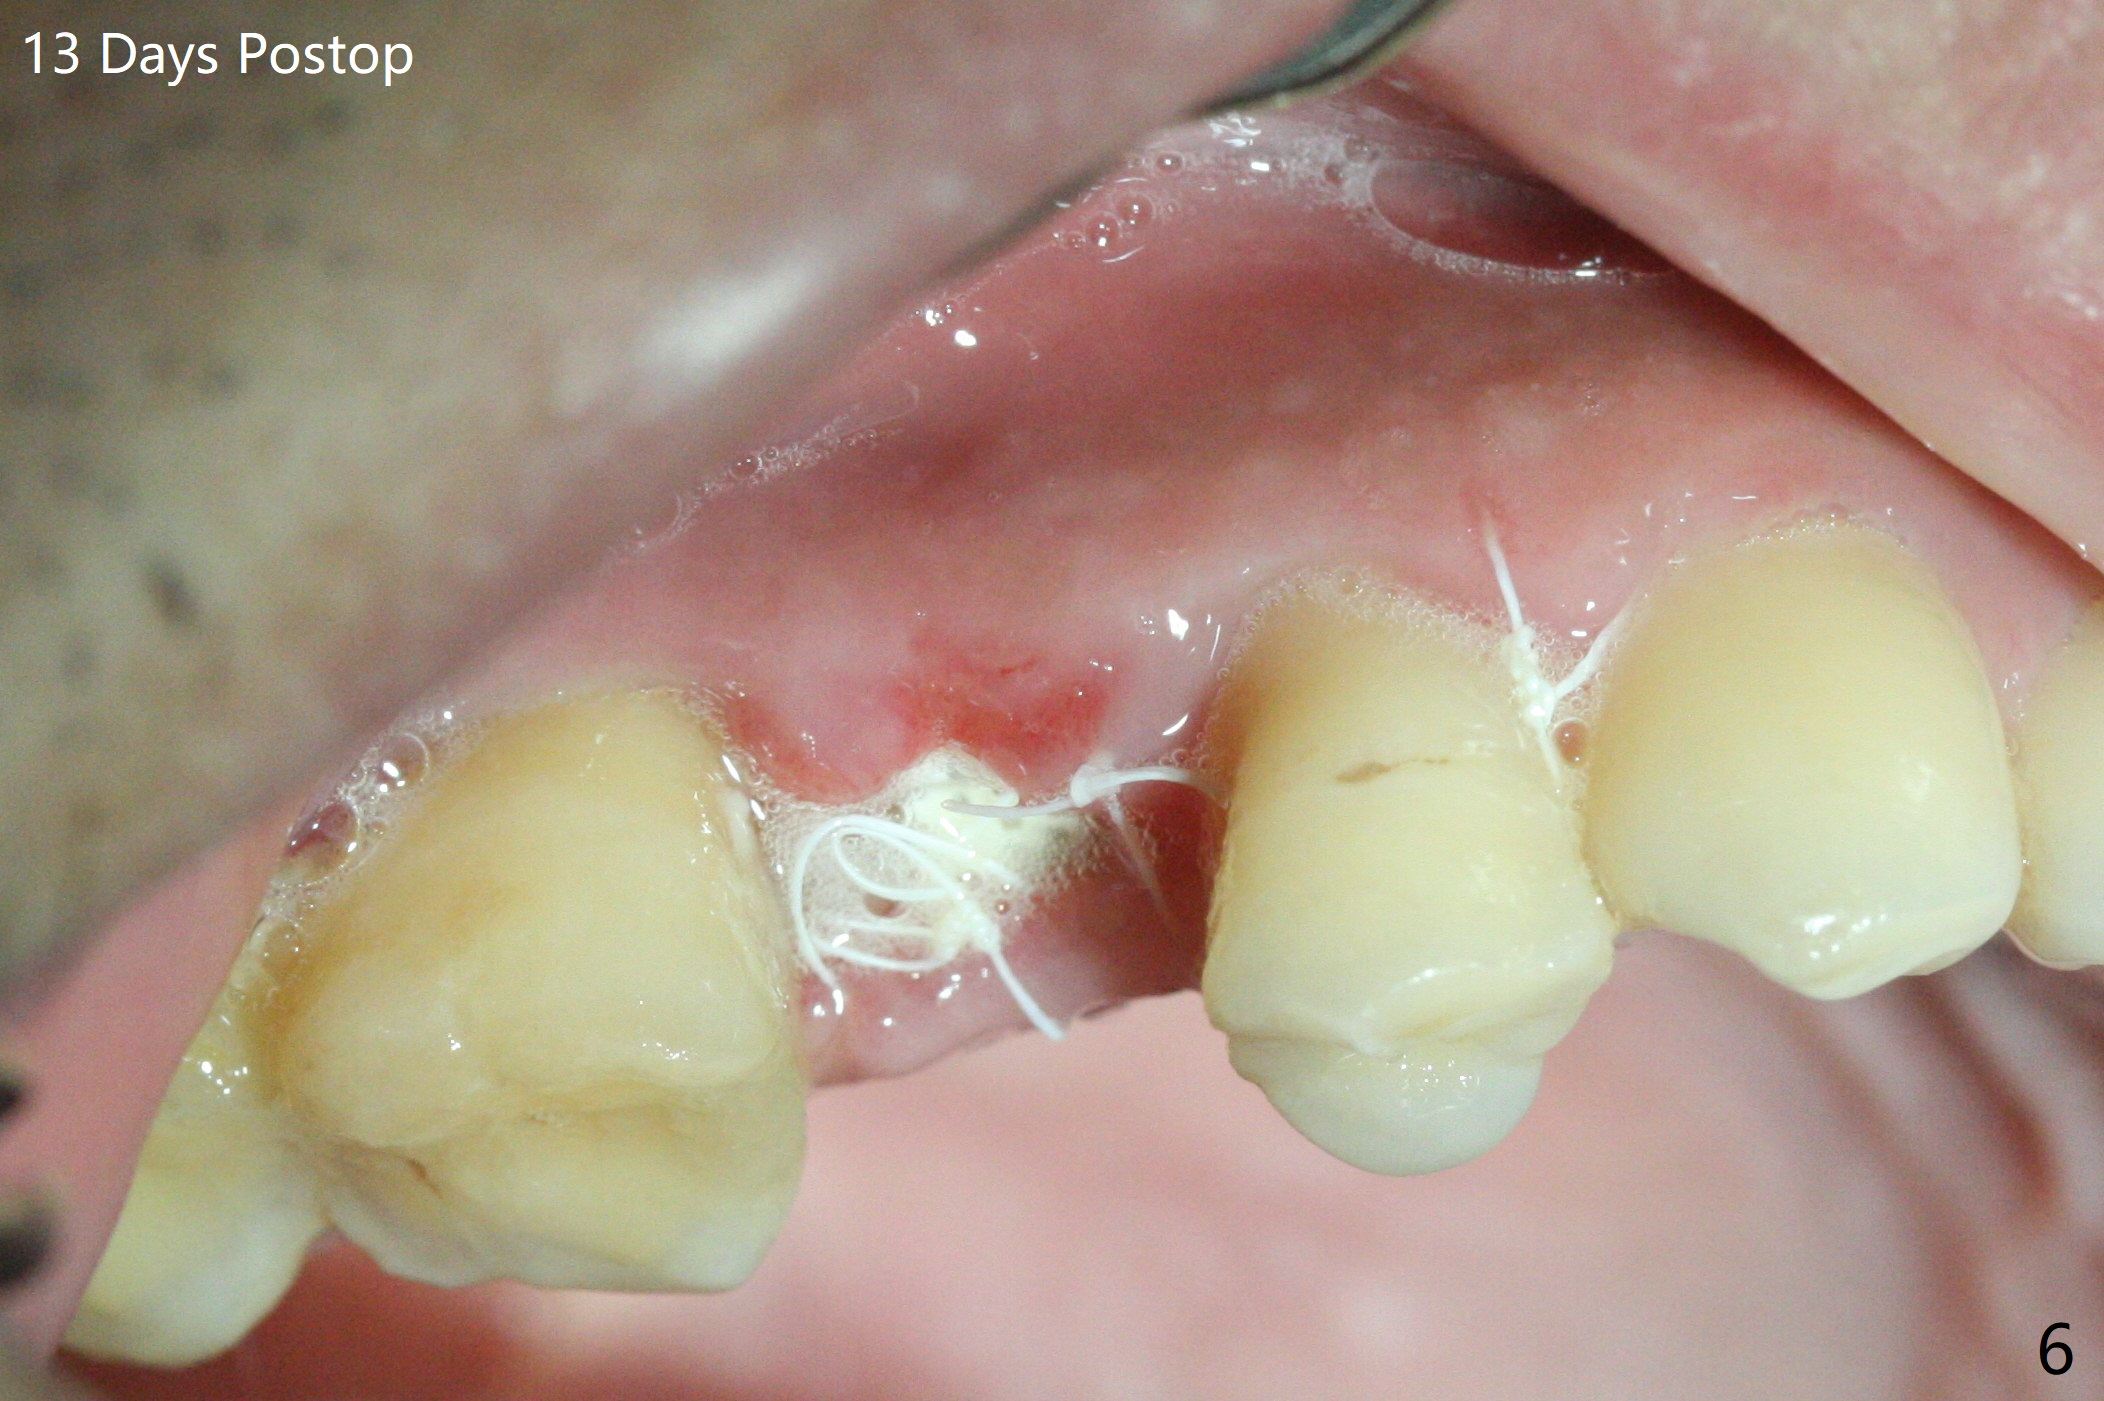

尽管没有任何症状,右上5牙冠粘固后2年5个月,牙冠与基台取出(没有使用扳手,说明基台未完全就位),切开,去除少量肉芽组织,仍然发现植体螺纹暴露(图一),使用一种叫I Brush 钛合金刷子清洁后,放置粘性骨块(图二: S),它坐在牙槽嵴上仿佛非常安稳,多么象马鞍(Saddle)。覆盖一张PRF膜和一小张Cytoplast(不可吸收膜,Osteogenics (company) 图三:箭头),使用PTFE缝线(与Cytoplast同样一种材料)缝合。术后即刻根尖片显示骨粉服服帖帖地坐落在植体和牙槽嵴上(图四:*)。最后覆盖牙周敷料。后者术后十天左右脱落,伤口愈合正常,颊侧瘘道仿佛消失,颊侧骨壁好像不再凹陷了(图五,六)。术后5周,膜已经脱落,缝线撤除后,伤口好像二期愈合,但愿肉芽组织下面骨粉尚未损失太多。术后三个月根尖片显示骨粉减少(图八)。不可吸收膜脱落可能造成骨粉流失。应该做减张缝合。术后4.5个月颊侧骨壁又凹陷(图九:箭头,需要decortication),但是uncover时植体周围都有骨质包绕,术后咬翼片也证明近中,远中骨质接触植体(图十:由于找不到合适愈合基台,直接放置基台和牙冠)。粘固后2.5个月虽然颊侧骨板凹陷,但是没有植体周围炎迹象(图十一)。